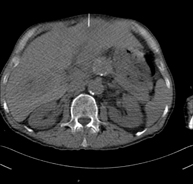

- Pelvis CT

Diagnostic test that involves obtaining high-definition anatomical two- and three-dimensional images of the pelvis (bone structures, vascular structures, bladder, uterus and ovaries, prostate and seminal vesicles, ureters, etc.) using CT (computed tomography) equipment. Most studies require the use of iodinated contrast.